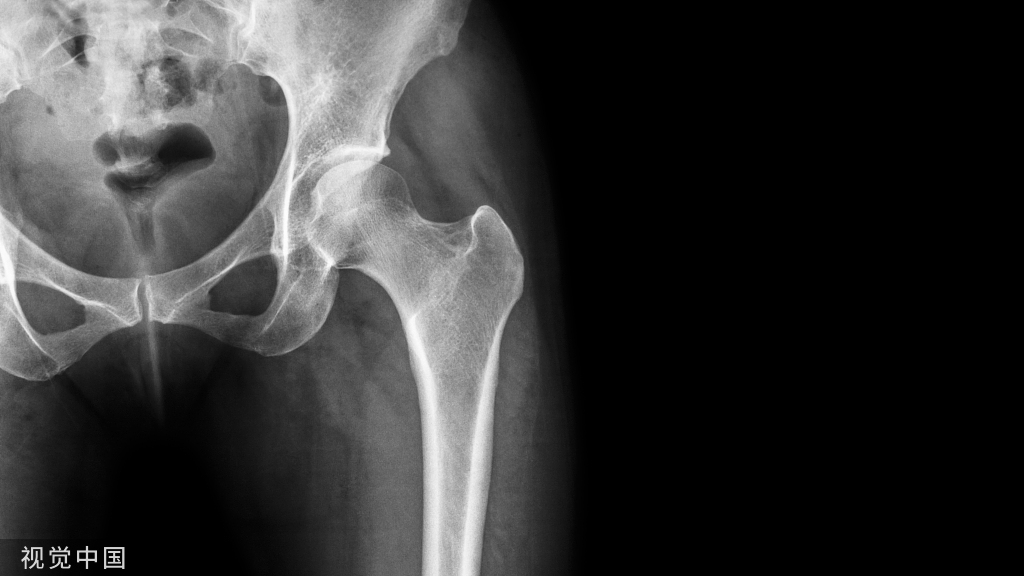

作为北京航空航天大学与北京积水潭医院医工交叉紧密结合的产物,公司成立于2017年,公司创始人王豫是北京航空航天大学生物医学工程学院副教授、院长助理、博士生导师。公司从骨科手术中难度最⼤、临床需求最强烈的⻣盆⻣折治疗出发,以数智化手段“复制”临床专家经验,研发的罗森万相®智能化手术机器人系统通过先进的数智算法,3分钟即可快速规划复位路径;强劲机械臂载荷160N,达成亚毫米误差的精准闭合复位,全程安全不需透线。

罗森博特®️智能化骨科手术机器人系统集合了目前医疗领域全高精尖技术,从创伤手术中难度最大、最依赖临床经验的骨盆骨折治疗出发,以3D实时导航、人工智能规划、自动手术操作等数字化技术,服务过去无法得到优质诊治的创伤骨折患者。

动态实时导航:精准导航定位,术中始终可见,帮助临床专家即时判断进针深度,实时引导复位全过程。

自动复位规划:通过大数据学习计算,快速高效复位规划算法,无需繁琐手工规划,将临床经验同机器算法深入结合。

自动手术操作:无需多人辅助暴露,通过力-位协同控制,实现全自动手术操作,更精准安全。

罗森博特团队通过建模仿真和实验测试,分析了骨盆骨折复位过程中的肌骨系统生物力学约束,以此为基础优化了复位规划、把持方式和工具设计,实现了复位力的高效传导,提高了机器人复位操作的安全性和有效性。